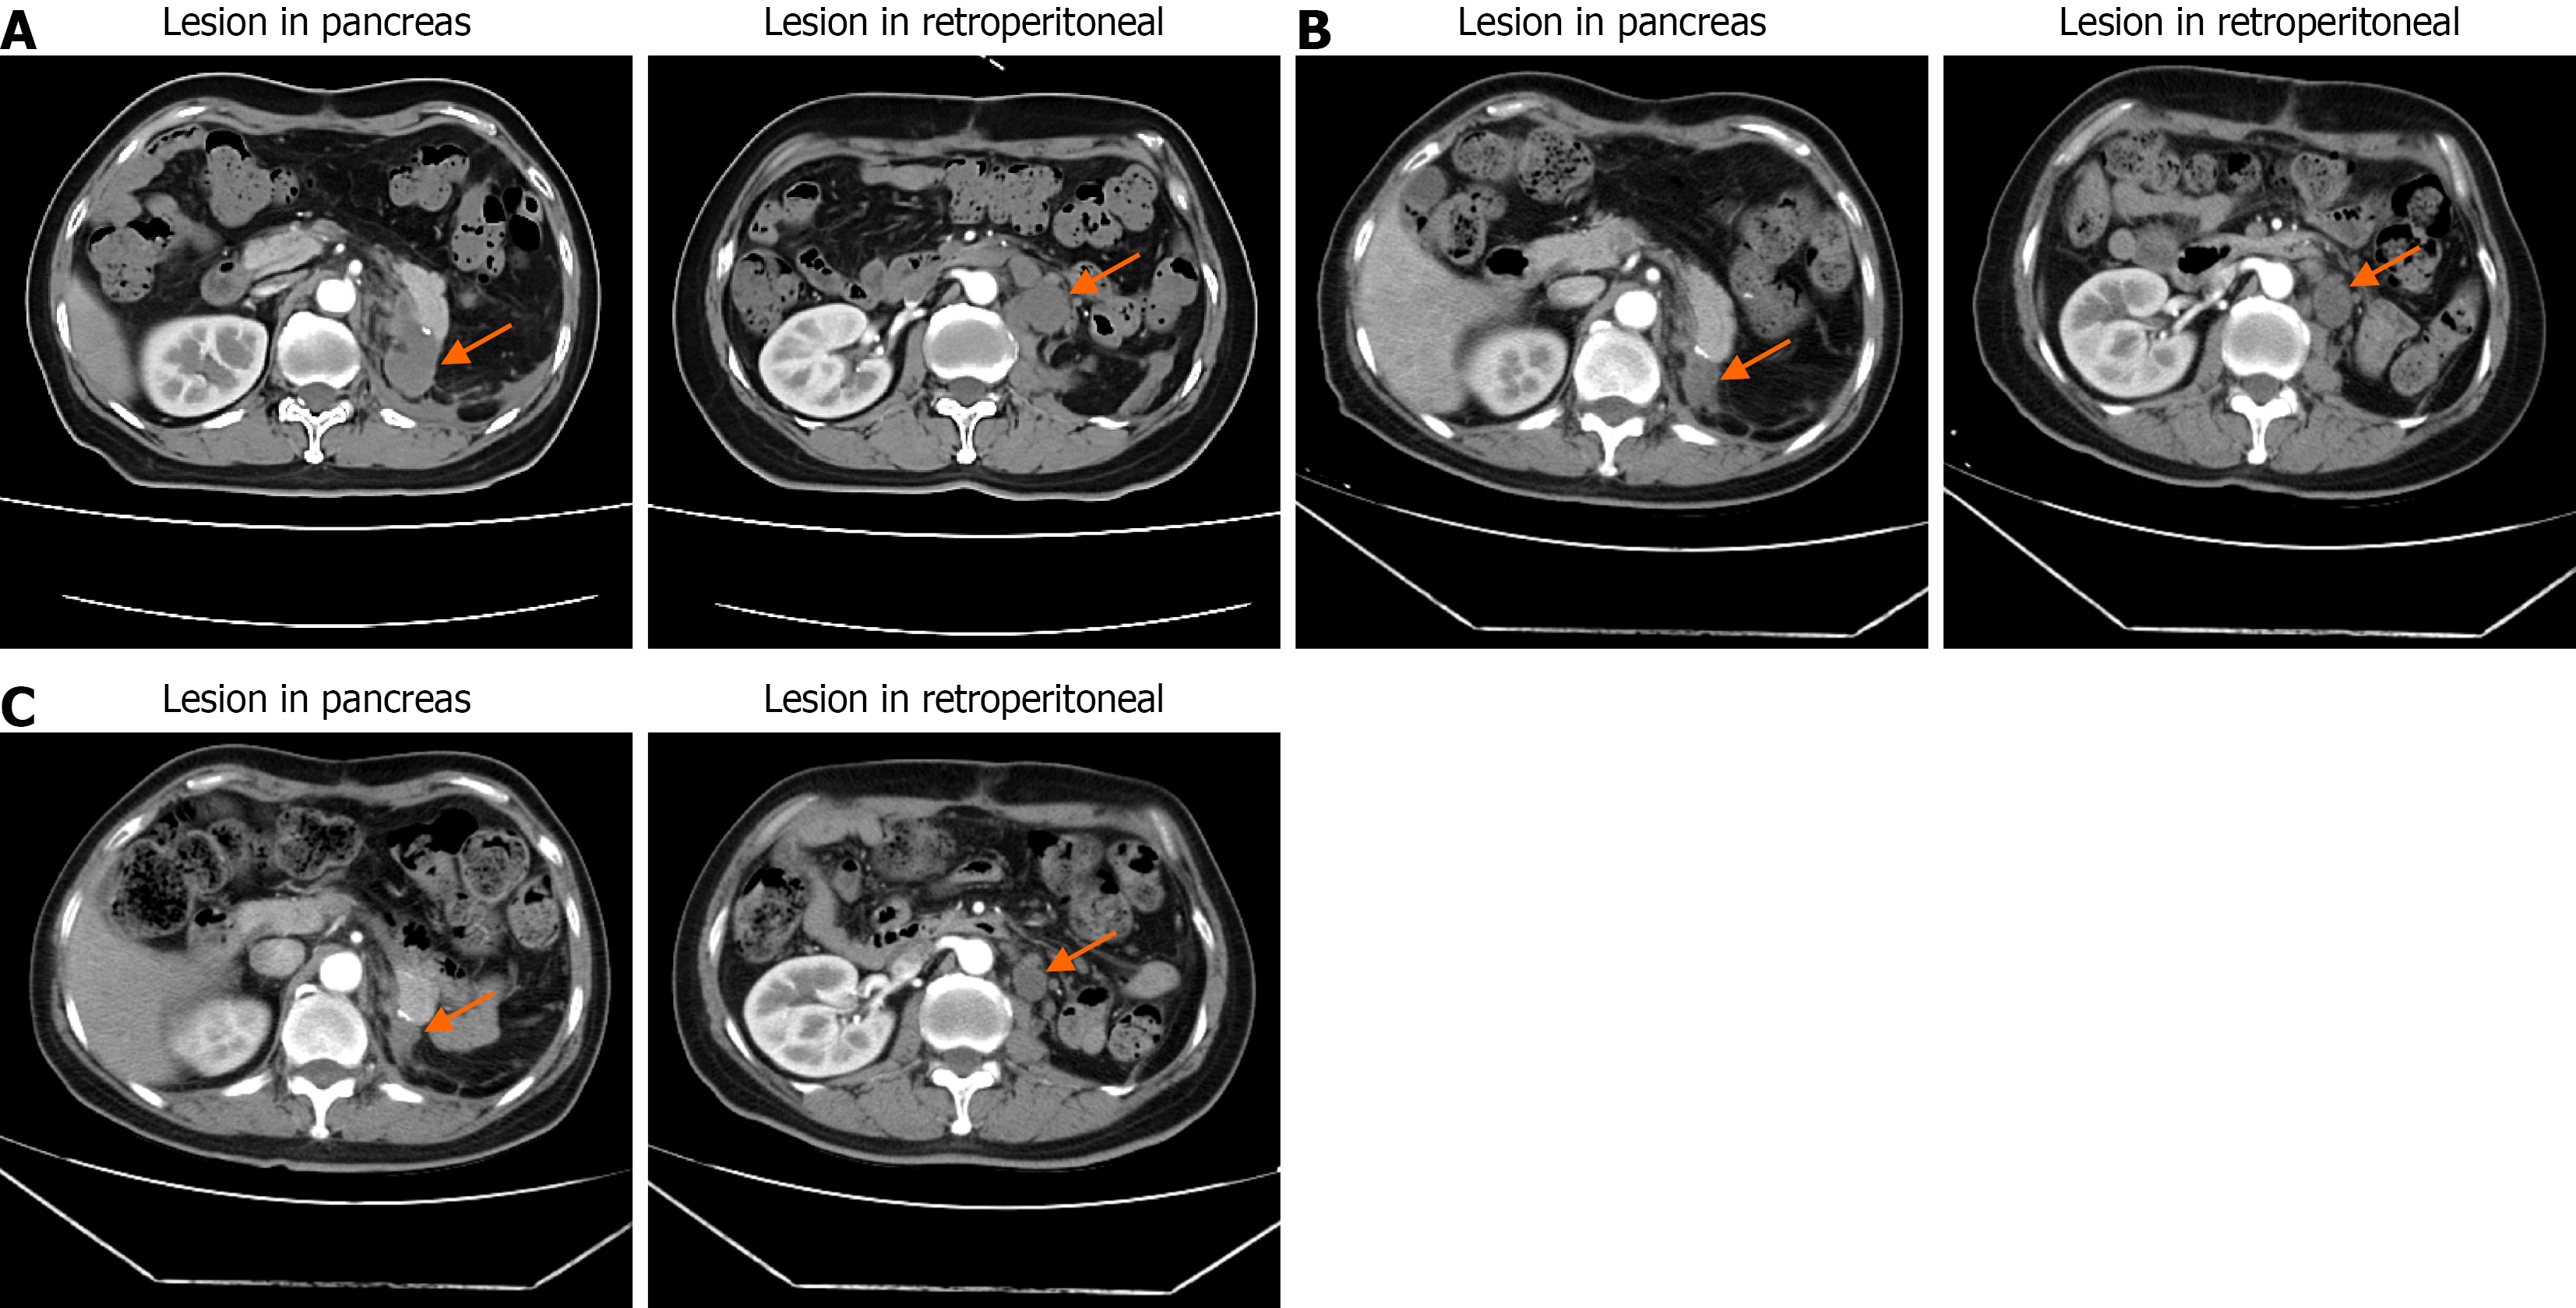

Figure 5 Representative computed tomography scans after surgery and during neoadjuvant therapy.

A: A recurrent mass at the pancreatic remnant and a retroperitoneal metastatic lesion after surgery; B and C: After neoadjuvant and targeted therapy, both the local recurrence and metastatic foci were reduced in size compared with pre-treatment imaging.